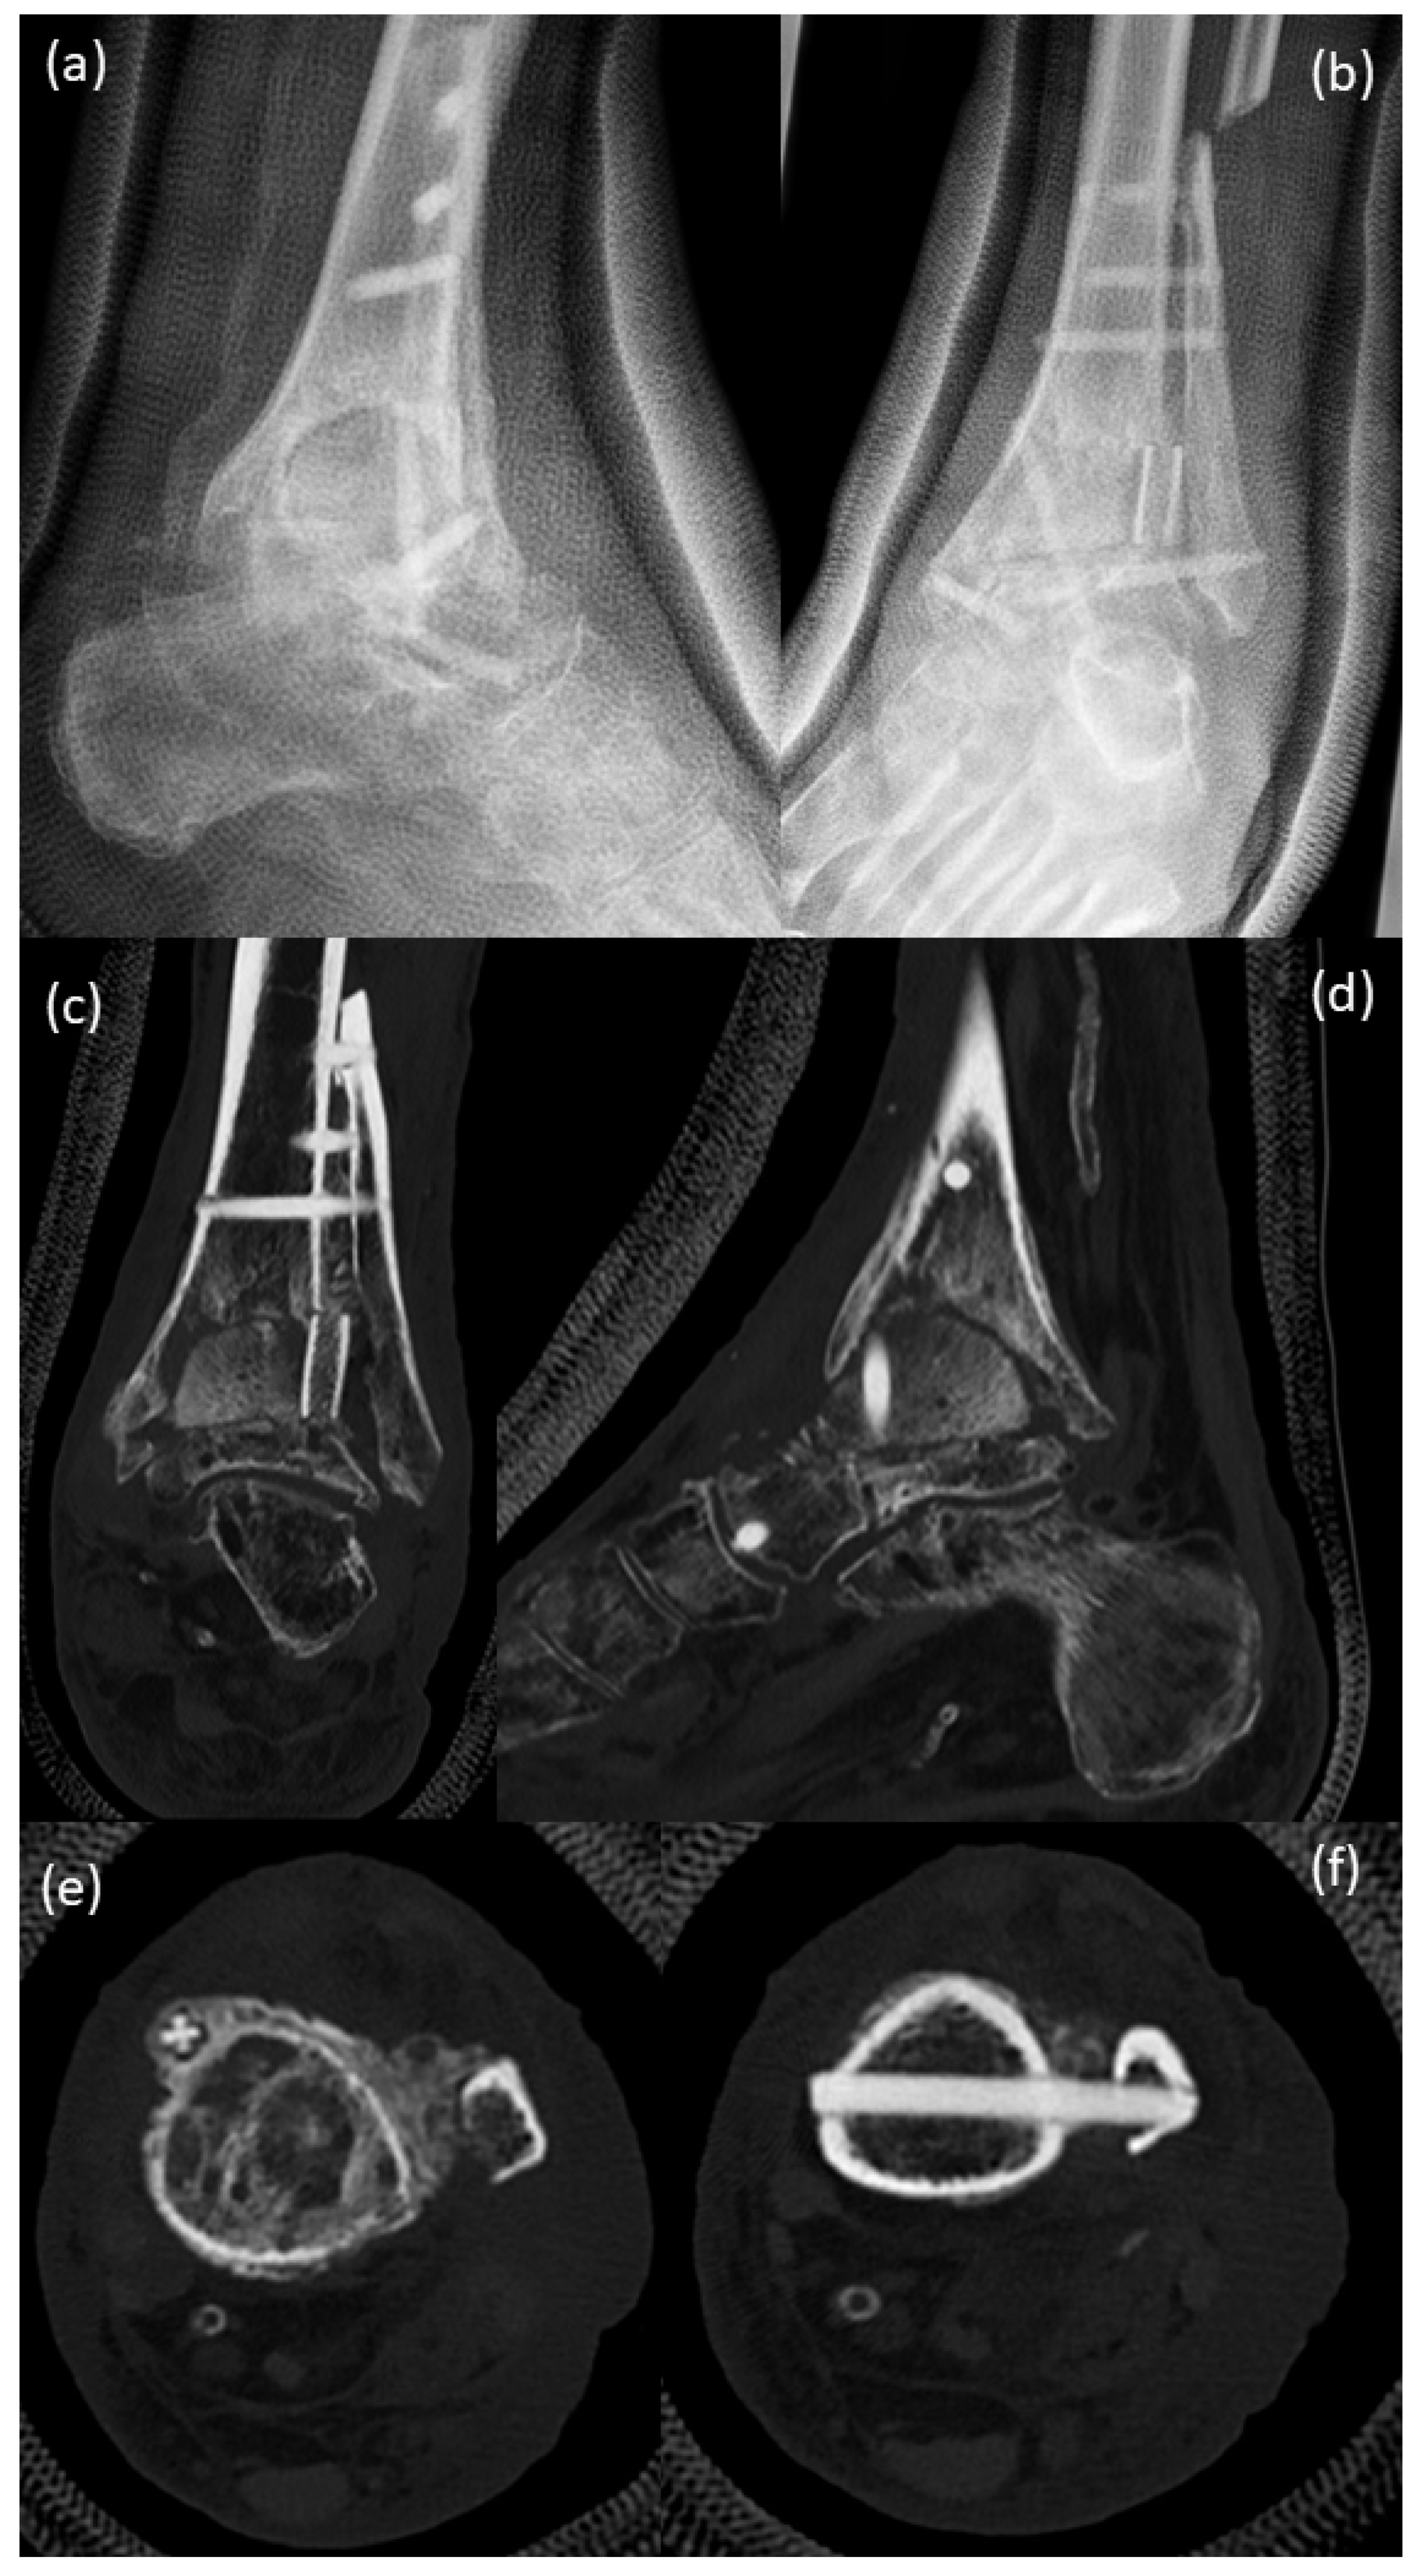

Twelve weeks after surgery (Figure 9), a clearly visible formation of callosal bone was seen around the screws, with a beginning of bony consolidation. CT scans support the X-ray findings.

Figure 9.

(a,b) X-ray; (c–f) CT scans 12 weeks after surgery with a clearly visible formation of callosal bone being seen around the screws with the beginning of bony consolidation.

One year after surgery (Figure 10), there was an extensive callosal bone superstructing the distal fibular and tibia. It is clearly seen that, in particular, the situation within the distal tibia and the talus was now in the status of good bony consolidation. No evidence of bone resorption or insufficiency of screws was obvious.

Figure 10.

(a,b) X-rays; (c–f) CT scans 1 year after surgery. There is extensive callosal bone superstructing the distal fibular and tibia. It is clearly seen that, in particular, the situation within the distal tibia and the talus is in the status of good bony consolidation. No evidence of bone resorption or insufficiency of screws can be seen.